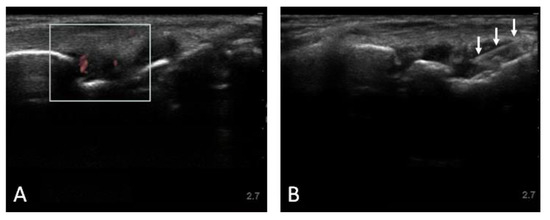

3.3. Ultrasound Examination